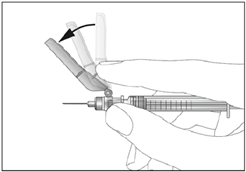

8. Drücken Sie das Schutzschild in Richtung Nadel (siehe Abbildung 11).

9. Positionieren Sie das Schutzschild im Winkel von ca. 45° auf einer ebenen Fläche (siehe Abbildung 12).

10. Drücken Sie die Nadel mit einer kräftigen, schnellen Bewegung nach unten, bis deutlich ein Klicken zu hören ist (siehe Abbildung 13).

11. Stellen Sie visuell sicher, dass die Nadel vollständig unter der Sperre im Schutzschild eingerastet ist (siehe Abbildung 14).